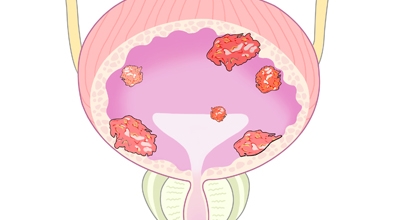

방광암이란

방광암은 여성보다 남성에게 발생할 확률이 상대적으로 높은 대표적 3대 비뇨기암으로 유명하고, 비뇨기계 암 중 발병률이 높아 남성암 중에선 7위라는 타이틀을 차지하고 있어요. 2017년 기준으로 보면 국내에서는 약 4400명이 방광암으로 진단받았으며 그중에서도 약 80프로가 고령 환자였다고 합니다.

정확한 비율로 따지자면 방관한 환자의 약 85프로 이상이 50대 이상의 연령에서 발견되었어요. 젊은 층보다는 연령대가 높은 중장년층에서 노인층까지 발병 확률이 높은 암이지요.